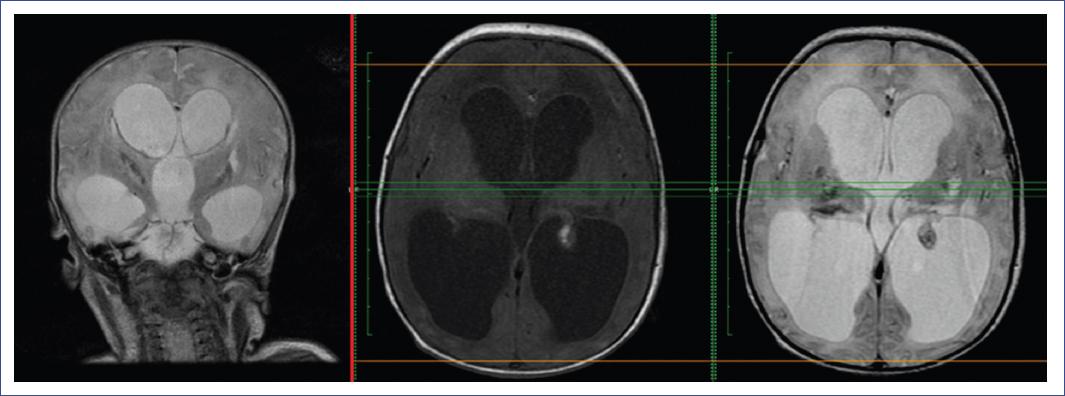

Producto de madre de 21 años, G1P1V1, con embarazo controlado y antecedentes de infección de vías urinarias y vaginosis. Parto vaginal a término y sin complicaciones. El producto egresa asintomático y permanece así durante la primera semana. Durante la segunda semana se advierten problemas en la alimentación, succión insistida y dificultad en la movilidad del brazo derecho. Acuden a consulta y se descarta fractura de clavícula, pero se presenta hipotonía global, sin llanto y cianosis, por lo que se sospecha cardiopatía. A su ingreso, se encuentra cianótico y con bradicardia, por lo cual se inicia soporte ventilatorio. Se observa un fenotipo llamativo con frente prominente, fontanela anterior amplia, diástasis de suturas, disminución del tamaño de los globos oculares, anisocoria leve, hipotonía grave y ausencia de reflejos primitivos (Moro). En la fundoscopia se evidencia hemorragia en el lado derecho. Ante el compromiso de encefalopatía de etiología no clara, se realizaron análisis de laboratorio con los siguientes resultados: plaquetas 105,000/mm3, aspartato aminotransferasa 61 U/l, alanina aminotransferasa 33 U/l, troponina 34 pg/ml (valores normales [VN]: 0-34.2), lactato deshidrogenasa 410 U/l (VN: 124-220), glucemia 267 mg/dl, creatinina 0.5 mg/dl, nitrógeno ureico en sangre 20 mg/dl, sodio 143 mmol/l, potasio 3.6 mmol/l, amonio 36 mmol/l, creatina fosfocinasa total 108 U/l, y VDRL negativo. El ecocardiograma y el electrocardiograma resultaron normales. Ante este cuadro de etiología no clara, se realizó una angiorresonancia cerebral en la que se observó hidrocefalia (Fig. 1).

Figura 1 Hallazgos de angiorresonancia cerebral. En las secuencias potenciadas en T1 se observa una imagen hiperintensa del plexo coroideo izquierdo, que sugiere un pequeño foco de sangrado intraventricular. Adicionalmente, se identifican imágenes puntiformes de alta señal en T1 (con baja señal en secuencias de susceptibilidad magnética), de localización córtico-subcortical y en ambas convexidades, al igual que en la región ganglio basal de manera bilateral. Estas señales corresponden a pequeños focos de sangrado intraparenquimatoso, y también se observan a nivel de las matrices germinales. El sistema ventricular presenta importante dilatación de los ventrículos laterales, en especial nivel de los cuernos occipitales, por signos de hidrocefalia no comunicante con alteración en la intensidad de señal de la sustancia blanca periventricular y áreas de alta señal en T2 que sugieren paso transependimario por hidrocefalia activa.